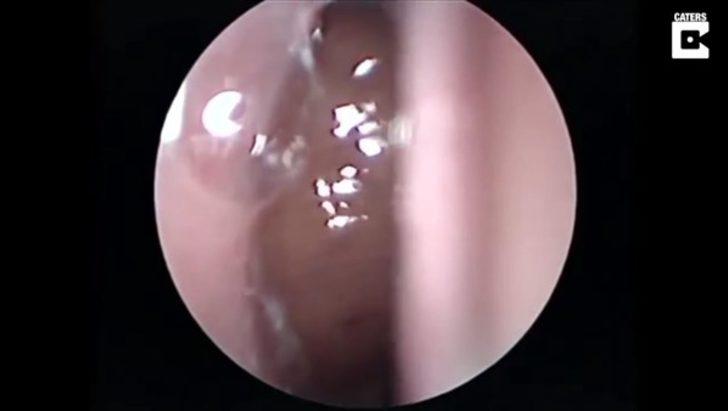

Burnunda garip bir hareketlilik hisseden hasta doktora göründü.

Doktor ise ufak bir operasyon yaptı.

Yüzerken burnuna kaçan şey doktorları bile şaşırttı